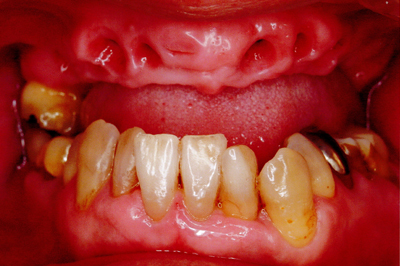

治療例2

歯ぐきが安定した状態

土台をたてた

噛める機能を回復

| ご費用 | 手術費用人工歯根 1本275,000円(税込) 上部構造 88,000円~110,000円(税込) |

|---|---|

| リスク・副作用 | 保険非適応(自費診療) 特定の全身疾患や持病のある方、顎骨密度の足りない方、妊娠中の方は手術ができない場合があります。 下顎のインプラント手術の際、偶発症のリスクがあります。 人工歯根が顎骨と癒着しないリスクがあります。 インプラント周囲炎になるリスクがあります。 |